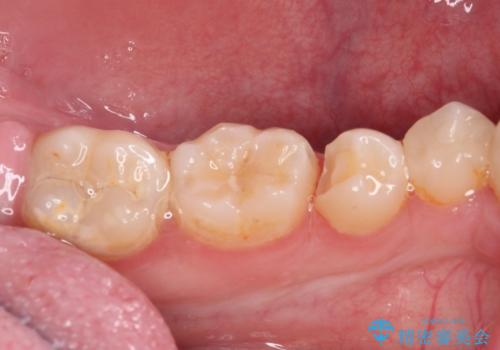

- 以前治療した詰め物が欠けてしまったことを主訴として来院した患者様です。

食べ物がはさまったり、冷たいものがしみるといった症状がみられました。

むし歯の染め出し液と拡大鏡を用いて、むし歯がないことを確認し、

セラミックインレーにて修復することとしました。